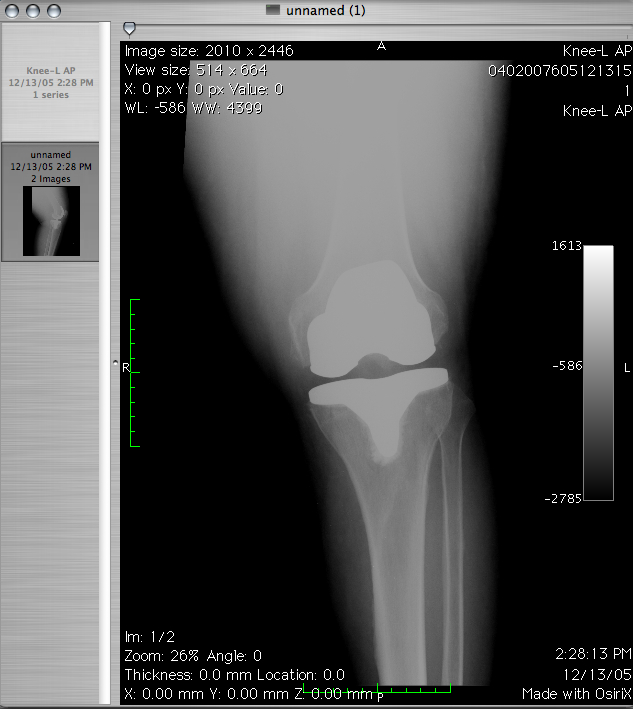

Jedną z szybciej rozwijających się dziedzin jest rehabilitacja. Nie wiedzieliśmy kiedyś jak wielki potencjał w …